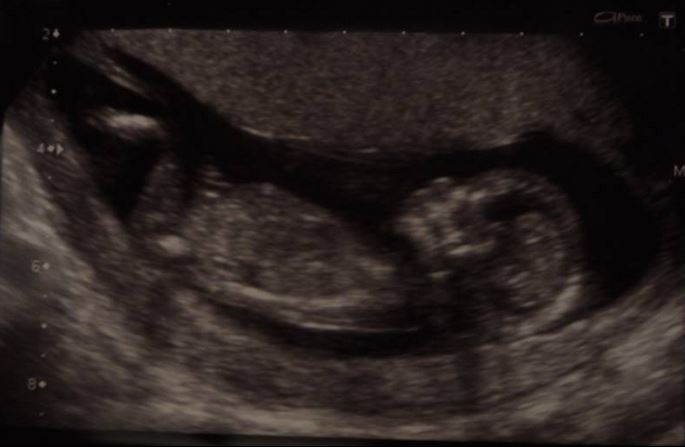

any clues anyone 13+ (for a family member and i'm dying to know!)

thank you, i'm not the best at this but i though girl (and that the nub was the faint line visible behind the leg?)

I don't really see a nub, but if it is that white area on (through?) the leg, then I can see why you think girl.... No angle. BUT it's also kinda big. I think it's still 50/50

Maybe girl but it's not an obvious nub x